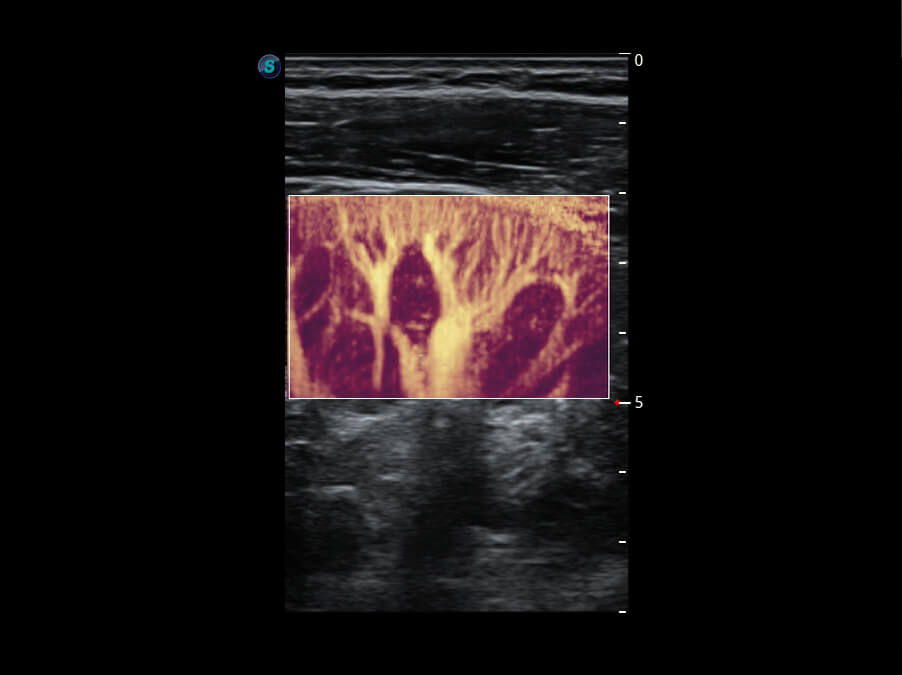

S60探头工艺,从前端信号处理每一个环节采集无损声学数据,真实还原组织原貌,再现解剖细节。

超宽频带技术,为容积成像带来优质的二维图像基础,为您呈现丰富的结构细节,栩栩如生地展示宝宝的宫内形态以及各种组织的立体结构。